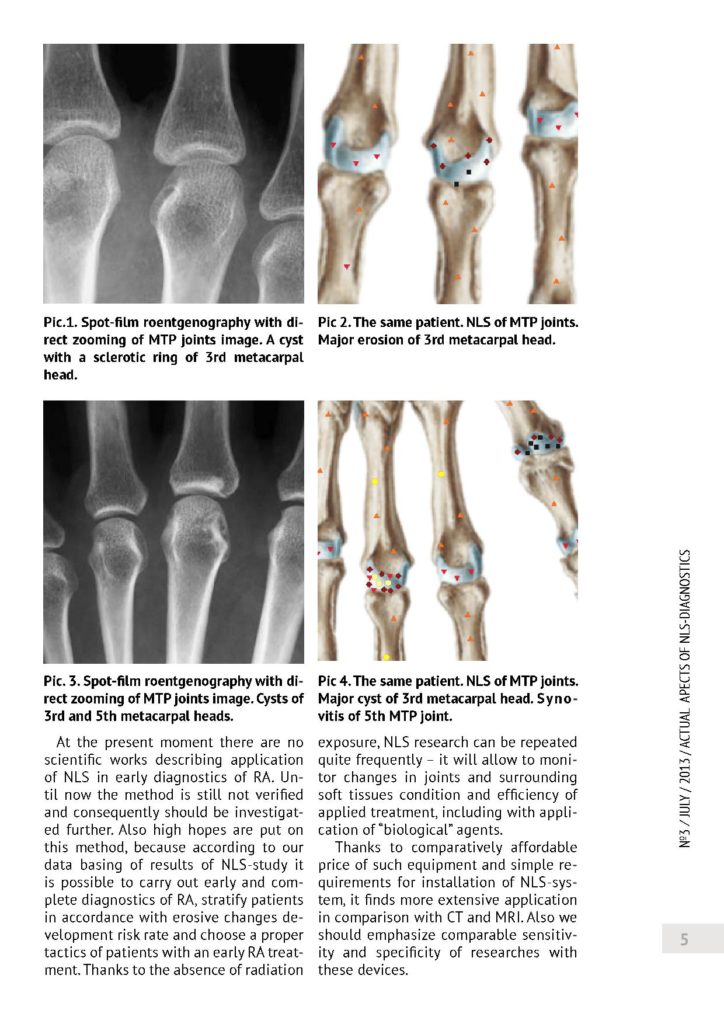

Trójwymiarowy NLS - w diagnostyce wczesnego reumatoidalnego zapalenia stawów